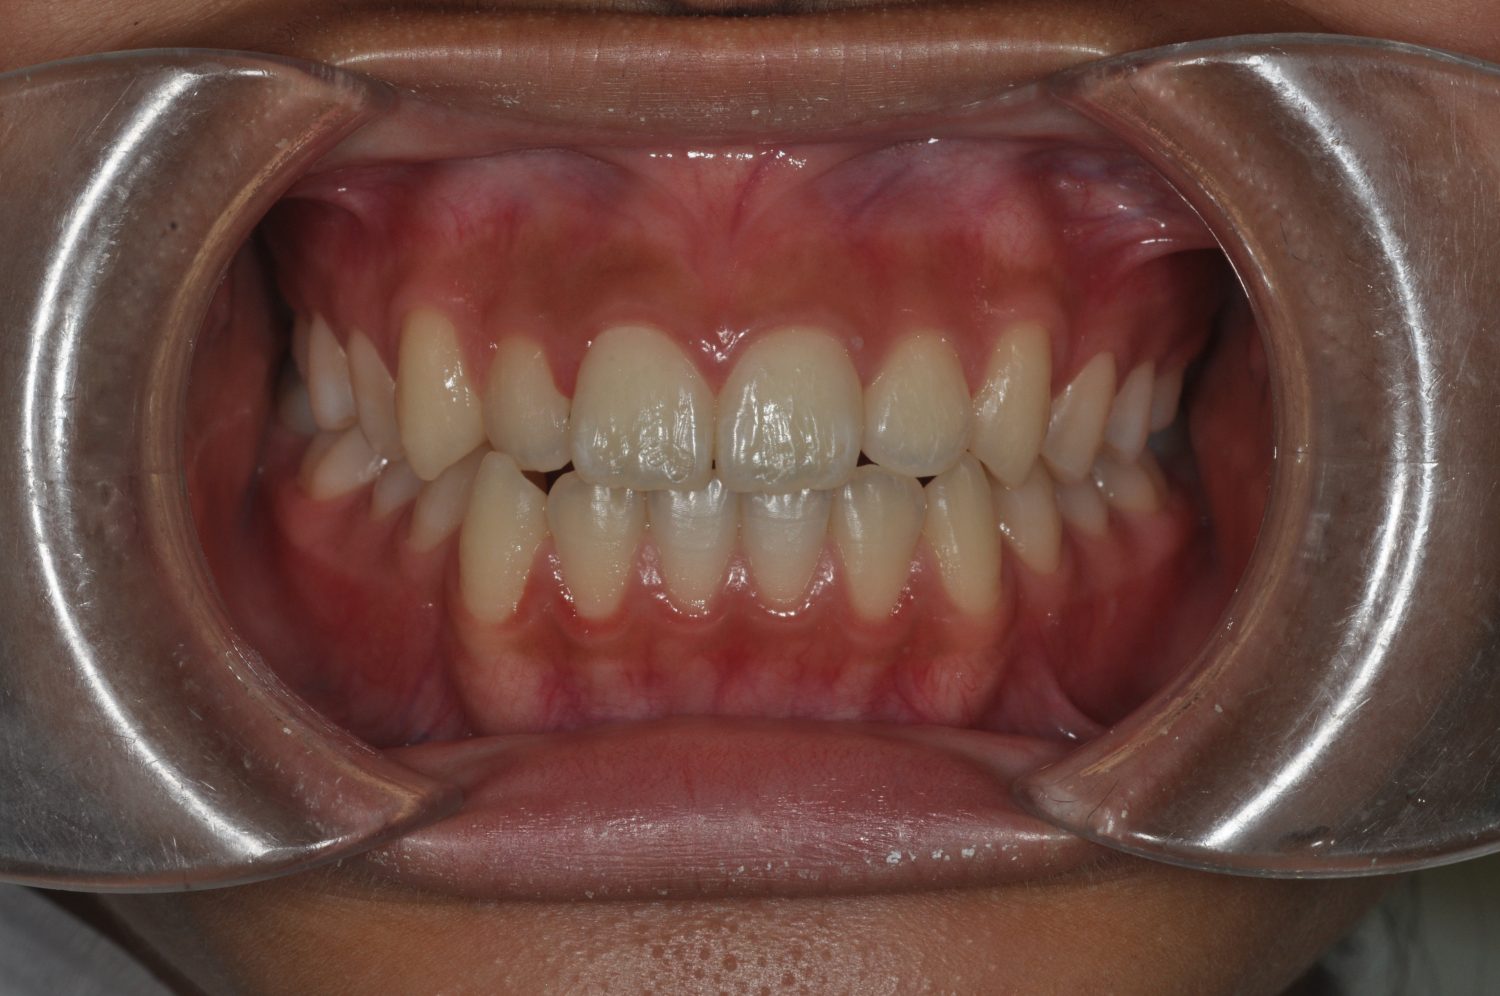

| 主訴 | 前歯部の叢生と正中の不一致 |

| 治療内容 | 軽度の叢生の改善を行うために、非抜歯でのマルチブラケット装置による治療を行った。 |

| 治療費 | Ⅱ期治療費:275,000円(税込) 調整料 5,500円(税込)×18回 保定時:22,000円(税込) 計 396,000円(税込) |

| 治療期間 | 2年2ヶ月 |

| 治療回数 | 20回 |

| 想定されたリスク | 矯正後に後戻りする可能性がありました。 |

Ⅰ期治療で叢生、反対咬合の改善をセクショナルアーチとMPAを使用して改善した後、成長観察を行っていました。永久歯の萌出したため、Ⅱ期治療を開始することとなった。上下顎とも骨格的に問題がなかったため、非抜歯で治療を行った。